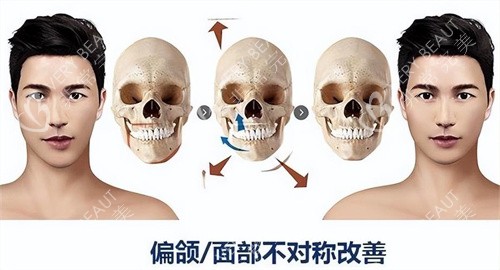

曾为一名车祸导致下巴歪斜的患者采用“三段式磨骨技术”,术后脸型对称度显著提升。

地包天矫正:22岁患者小丽因下颌前突长期自卑,何锦泉通过上下颌根间截骨术+颏成型术,将下颌骨后推至正常位置。

术后她的面部轮廓修复自然,咬合功能显著改善。

复杂颅颌面修复:一位因瘤切除导致面部塌陷的患者,何锦泉通过自体骨移植+3D导板定位,成功重建面部轮廓,术后外观与术前模拟结果几乎一致。

一位偏颌患者反馈:“何医生调整截骨量时反复比对两侧对称性,术后朋友都说我像‘天生丽质’。